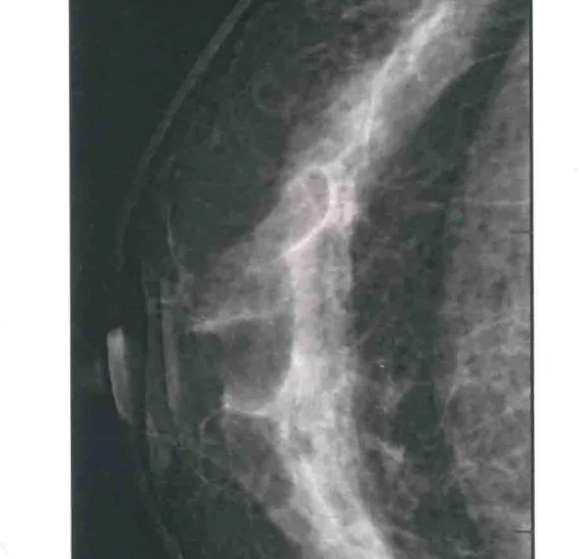

乳腺DR头尾位/CC位检查方法

二、图像显示要求,含乳腺的基底部及内外侧乳腺组织,需要显示胸肌前缘或胸壁。头尾位与内外斜位乳头后线长度差≤1厘米;显示实质后的乳腺组织,乳头位于切线位,乳腺组织重叠;双侧乳腺头尾位照片相对放置,则两侧乳腺呈球形;影像密度和对比度良好,能显示0.1毫米细小钙化,清晰没有伪影异物、运动伪影和切割伪影等。